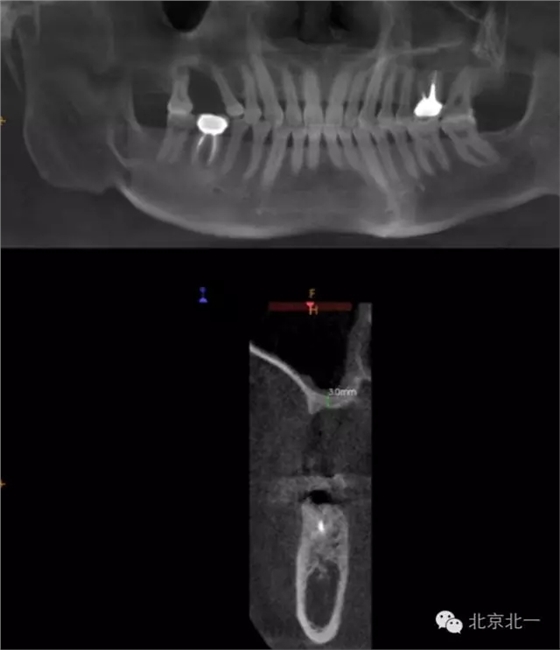

CBCT顯示,骨寬度可,骨高度不足,月3mm。頜間距離增大。

圖二:手術前全景片

圖三:骨高度3mm.

圖十八:手術前CBCT

圖十九:手術后當天CBCT